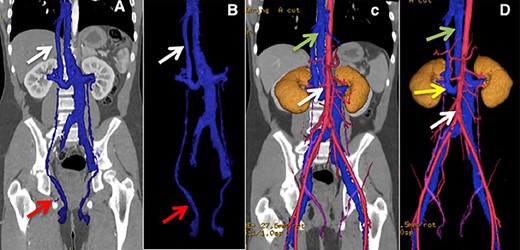

A 14-year-old male, without relevant history, consulted the urologist for enuresis and was diagnosed with the right varicocele. CT angiography was performed, showing an IVC anomaly, with partial hypoplasia of the upper segment, persistence of the left SVC to which the left and right renal veins drain, the left renal vein with a retro-aortic segment showing signs of aorto-vertebral impingement, a right dilated and tortuous testicular vein ending in the right renal vein and continuation of the azygos in the visualized thoracic segment. (Fig. 2).

(A and B) Lower arrow shows testicular vein, upper arrow shows hypoplastic suprahepatic segment of the IVC. (C) Lower arrow shows aorta, upper arrow indicates azygos vein. (D) Lower arrow shows aorta, middle arrow shows retro-aortic right renal vein, upper arrow shows azygos vein.